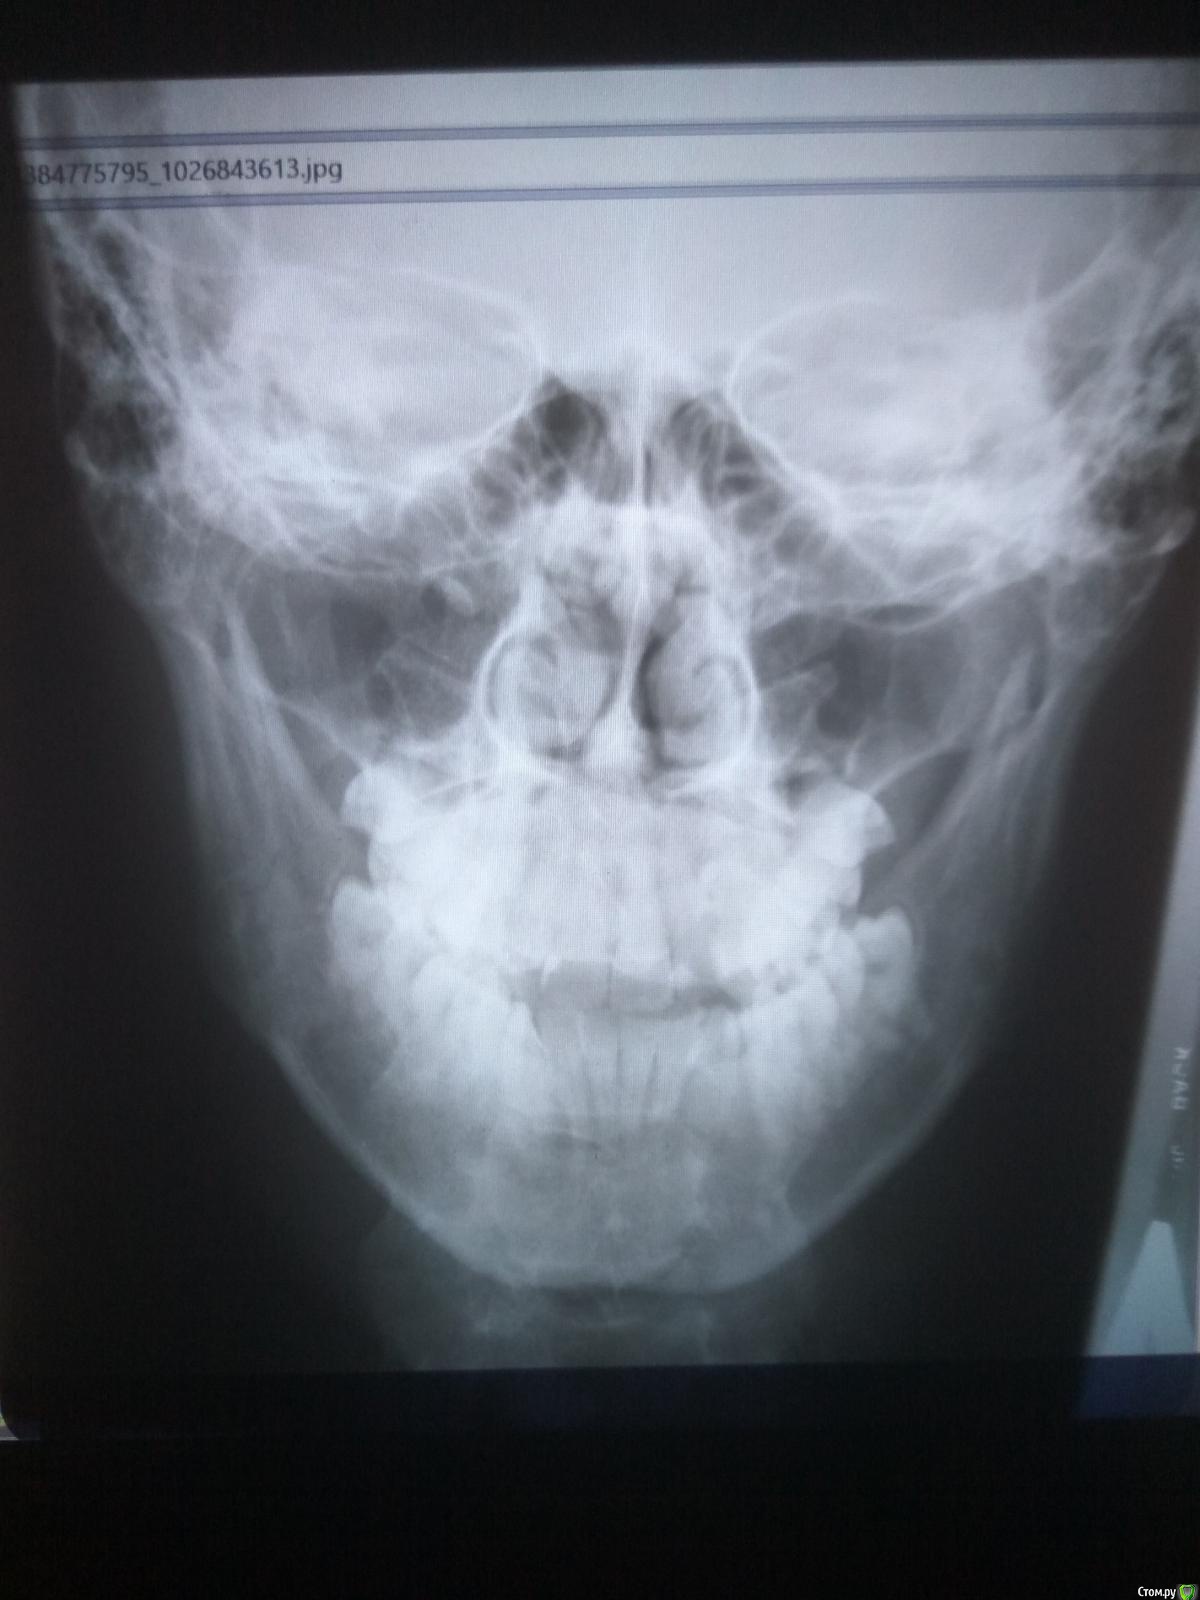

eventpromo Опубликовано 7 ноября, 2016 Поделиться Опубликовано 7 ноября, 2016 У меня перелом нижней челюсти справа (получил 1 удар 05.11.16), ношу повязку, не жую, постоянно полоскаю миромистином и ополаскивателем, питаюсь жидким и колю антибиотики (Цефазолин). Хотелось бы узнать на сколько сложный у меня перелом, есть ли шанс, что при очень ограниченной подвижности челюсти оно зарастет само? А зуб удалить после того как срастется челюсть. У меня запланирована очень важная недельная поездка на 3-ее декабря. Ехать в нее с шинами - невозможно. Допустим, если мне необходим будет остеосинтез, можно ли будет обойтись без шинирования? Какова приблизительная стоимость остеосинтеза в моем случае? Возможен ли внутренний разрез? Какой срок заживления после синтеза? В идеале хотелось бы надеяться, что при особом уходе оно сможет зажить без шин и операции. Фото снимков в лучшем качестве и заключения:http://rusfolder.com/45397566 КТ:http://rusfolder.com/45397567 Спасибо за Ваши ответы. Ссылка на комментарий

eventpromo Опубликовано 29 ноября, 2016 Автор Поделиться Опубликовано 29 ноября, 2016 Все здравстувйте, в пятницу мне по расписанию должны были снимать иммобилизацию.Но сегодня я сделал КТ и мне сообщил врач-рентгенолог плохую вещь:Раннее выявленная косая линия перелома ветви нижней челюсти справа сохраняется, смещение костных отломков и формирование костной мозоли не отмечается, в сравнении с данными от 19.11.2016 определяется незначительное расширение линии перелома.Прошу вас посмотреть новые результаты КТ от 30.11.2016:https://drive.google.com/open?id=0B7O2C3xQGuKmRW80V2JvdnlsdHM Результаты от 19.11.2016:https://drive.google.com/open?id=0B7O2C3xQGuKmSEJ4Z2dPMmlncmM Почему кость не срастается, в чем может быть причина и что необходимо делать далее? Почему вообще ситуация стала еще хуже, чем была?Что необходимо делать дальше? Сколько нужно еще ходить с фиксацией? Я очень расстроился, надеялся, что скоро все сниму! Ссылка на комментарий

eventpromo Опубликовано 30 ноября, 2016 Автор Поделиться Опубликовано 30 ноября, 2016 Выложите пожалуйста сканы как вы это сделали 19.11.16. качать КТ полностью многие не будут. По поводу онемения щеки - если спустя месяц после снятия шин ощущения сохронятся - есть смысл искать из-за чего, пока во рту много инородного (+ субъективные ощущения этого) - смысла как такового нет. Сканы от 19.11.16: Сканы от 30.11.16: Не могу понять, то ли качество было 19-го хуже, то ли там был прогресс. а сейчас регресс. Ссылка на комментарий

___49___ Опубликовано 30 ноября, 2016 Поделиться Опубликовано 30 ноября, 2016 (изменено) Ничего критичного не вижу. очень незначительное доп смещение можно отнести к тяге жевательной мускулатуры не закрепленного отломка ( ветвь нижней челюсти в принципе при данной методике не имеет жесткой фиксации и это нормально ) в пределах допустимого и скорее всего не повлияет на функцию Зубо Челюстной Системы в будущем. я бы счел за радость будь хотя бы у половины пациентов с диагнозом перелом Н/Ч такая ситуация с отломками как у вас. Изменено 30 ноября, 2016 пользователем ___49___ 1 Ссылка на комментарий